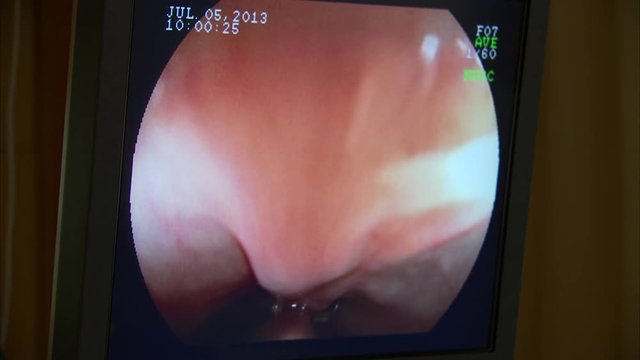

27,216 results for panendoscopy in all

View panendoscopy in videos (6329)